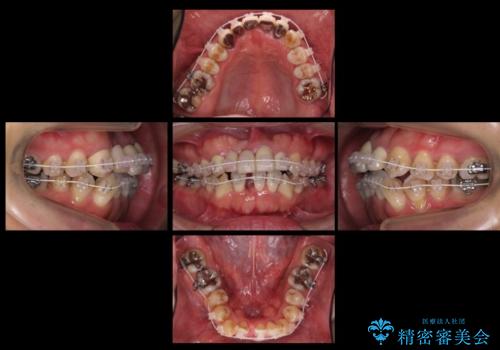

- 前歯のブリッジのやりかえおよび銀の詰め物をセラミックにしたいと来院。

過去に事故で前歯を折って、ブリッジにしたとのことでしたが、支台となる歯が持たない状況で、ブリッジを延長せざるを得ない状況でした。

長いブリッジへ設計変更になるため、下の前歯のがたつきが気になるのであれば、先に矯正治療をしてから最終的なブリッジを入れることをご提案し、全て行なっていくことになりました。

上の前歯の本数が少ないことから、小臼歯を4本抜歯するのではなく下の前歯を1本だけ減らして並べました。